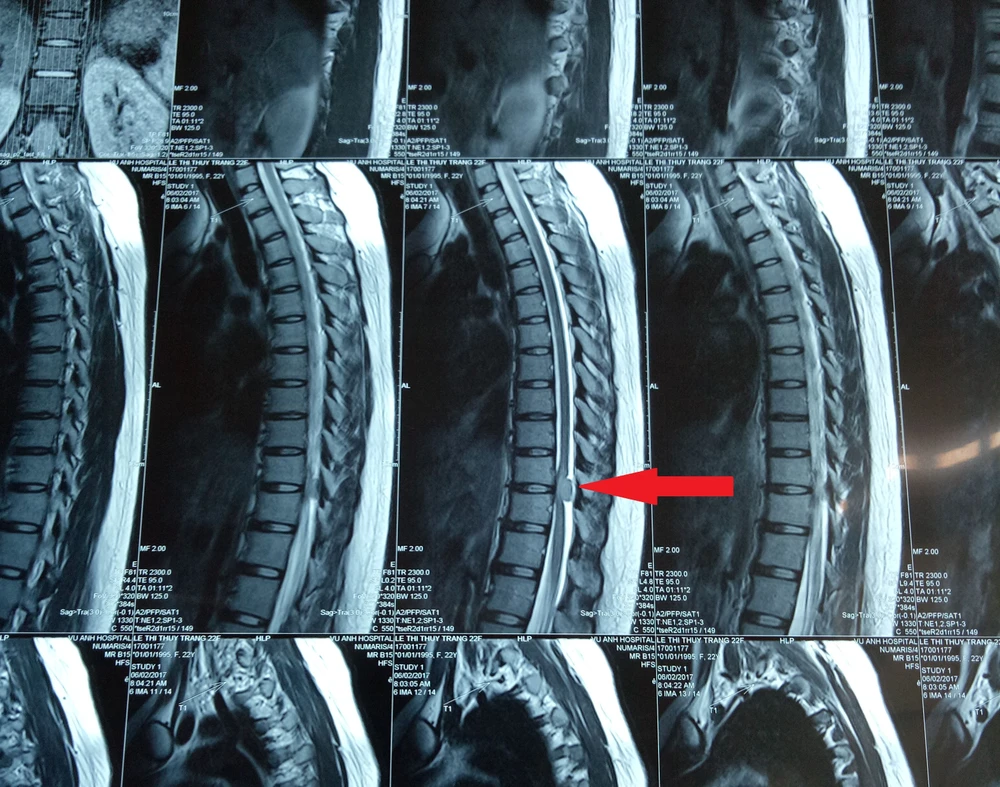

Kết quả chụp X-quang ghi nhận bệnh nhân bị u tủy sống ngực đoạn D10-D11 (mũi tên). Ảnh: ĐÌNH CHI

Sau khi thực hiện các chỉ định cận lâm sàng như chụp X-quang, MRI, BS chẩn đoán bệnh nhân bị u não tủy sống ngực đoạn D10-D11. Sau khi được BS tư vấn, bệnh nhân đồng ý nhập viện để phẫu thuật khối u.